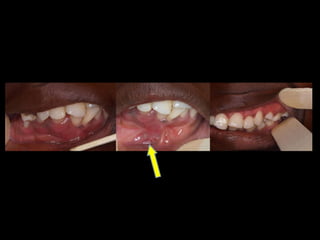

Hiperplasia condílea dcha

Anquilosis ATM dcha